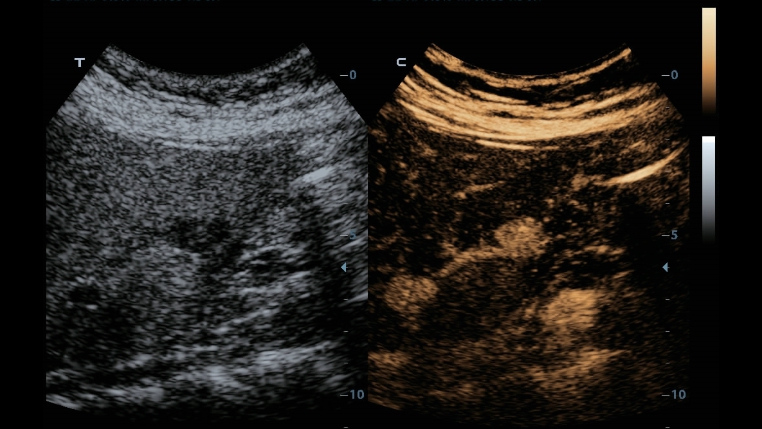

ComboWave ?????

?? ?????? ???? ComboWave ?????? ??? ??? ?? ?? ??? ???? ?? ????? ??? ????? ?? ????? ??????. ????? ??? 3T ??? ?? ??? ComboWave ??? ?????? ???? ???, ??, ?? ??? ??? ?? ???? ????? ??? ??? ??? ? ????.